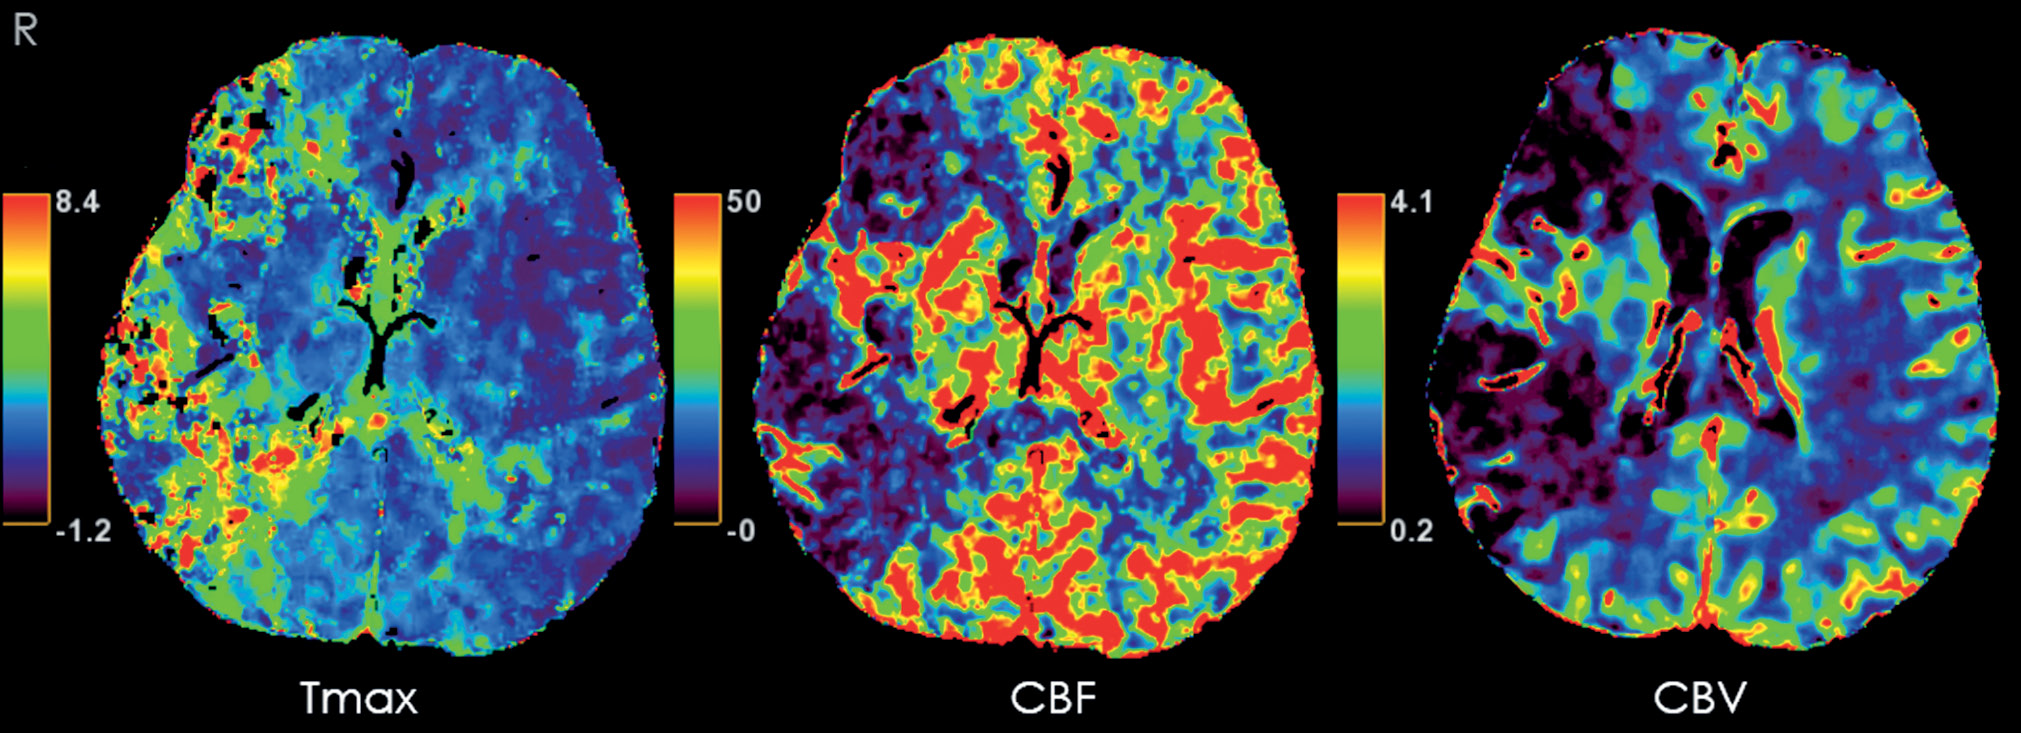

Компьютерная томографическая ангиография с оценкой перфузии. По данным рентгеновской компьютерной томографической ангиографии, участков выраженных стенозов в брахиоцефальных артериях не выявлялось, отмечалось обеднение кровотока в дистальных ветвях правой СМА, значимых изменений показателей перфузии (рис. 2) интактного, по данным МРТ, вещества головного мозга выявлено не было.

Рис. 2. Карты перфузии в аксиальной плоскости на уровне поражения, по данным компьютерной томографии. Отмечается снижение перфузии, характерное для постинфарктных изменений, в зонах, соответствующих кистозно-глиозной перестройке: Tmax (время до максимума функции вычета, с); CBF (скорость кровотока, мл/100 г×мин); CBV (объём кровотока, мл/100 г).